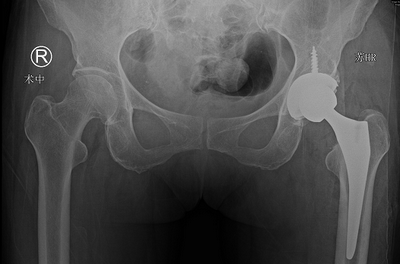

在sararz关节外科,蒋守海主任医师为张大妈进行了系统检查,结合相关影片判断其左股骨颈骨折。听说自己骨折了,张大妈也不禁担心起来,家里一堆事儿,这伤筋动骨几个月可咋整……为了让张大妈尽快恢复,手术团队在结合病情讨论及与家属的充分沟通后,决定在Mako机器人的辅助下,为张大妈进行治疗。

在Mako机器人的辅助下,张大妈的手术进行的很成功,不到1.5小时就完成了髋关节置换手术,目前正在进行康复锻炼,很快就可以回归正常生活。